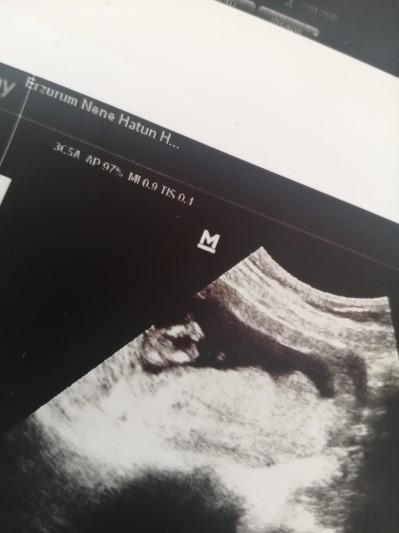

Kızlar erkekmi kızmı anlayan varmı acaba

Gebelik haftası 13+5

Erkeğin çıkıntısı daha fazla olur diye düşünüyorum görür görmez kız gibi geldi doktorunuz ne söyledi

Düzgün çekseydin canim tam net siyah beyaz karışık diye bilinmiyor

Garip bir şekilde ben erkeğe benzettim eğer kordon değilse